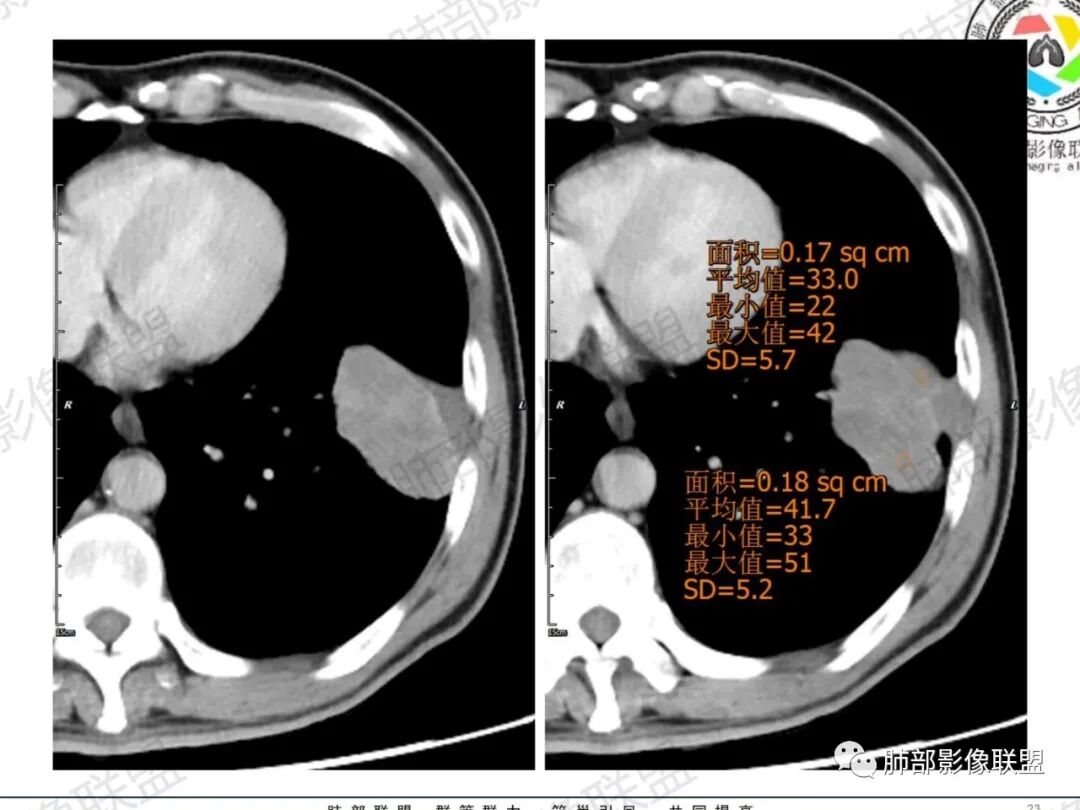

一切∮随缘:左肺下叶不规则肿块,边缘光滑,平直,局部彭隆,分叶,近端支气管堵塞,远端与胸膜相贴,平扫密度尚均匀,增强后不均匀强化,内部可见低密度坏死,胸膜下多发肺气肿,伴双肺散在光滑小结节,实验室肿瘤标志物高,考虑恶性:神经内分泌癌(大细胞),腺癌,鳞癌。

琦遇:恶性没有问题,肺气肿底子、病灶分叶、少许毛刺、叶间胸膜凹陷、部分边缘可见清晰的GGO、胸膜牵拉凹陷、局部胸水、近端支气管截断、部分支气管被推移、占位效应明显、强化特点为不均匀强化、内部有少许沼泽样低强化区,强化部分轻中强化为主、余肺可见转移性结节、左肺上叶似为囊腔型腺癌一枚,肿瘤标志物提示非小、神经内分泌,综合分析考虑大神泌、腺癌、腺鳞癌、鳞癌  同时左肺上叶囊腔型腺癌  肺转移

飞鹰行动:中年人,男性,胸疼入院,左肺下叶占位,张力较高,边界可见分叶,局部可见明显收缩性改变,增强病灶内部有延迟强化表现,考虑恶性病变,大细胞癌伴肺内转移或者囊腔样腺癌伴转移。

蕊:中老年男性,吸烟史,肺气肿背景,左肺上叶类圆形肿块影,边界清晰,边缘凹凸不平,有分叶,支气管进入阻断,临近胸膜栽赃,整体病灶膨隆,局部周围可以清晰ggo,临近叶间裂内凹,轻度强化,并可见多个低密度区,坏死可能,界线不清;肺内多结节,边缘光滑,考虑恶性伴转移,鳞癌、腺癌

傅昌瑜:中老年男性,肺气肿背景,右胸背疼痛1周。CEA、NSE、CYFRA—211升高。左上肺混合磨玻璃结节,内见较多空泡和扩张支气管。左下肺胸膜下肿块,边缘较光滑,深分叶,似有血管进入,与支气管关系不清,内见不均匀强化,见沼泽地样坏死,有胸膜栽赃。另两肺多发圆形小结节。考虑恶性并肺内转移,多原发可能性大,左上肺腺癌,左下肺病理难以判断,小细胞癌?鳞癌?

小锁:中老年男性,肺气肿背景,右胸背疼痛1周。CEA、NSE、CYFRA—211升高。左上肺混合磨玻璃结节,边界清楚,内见较多空泡。左下肺肿块,边缘清楚,深分叶,有血管和支气管进入,胸膜凹陷。另两肺多发圆形小结节。考虑双发原位癌,左上肺腺癌,左下肺大神泌或腺鳞癌可能,肺内转移。

蓝天白云:中年男性,肺气肿背景,左肺下叶肿块,边缘膨隆,有分叶,内有湖泊样坏死,有轻中度强化,局部胸膜栽赃,收缩力不强,周围见肺气肿征象。左肺上叶混合磨玻璃影,边界清楚,考虑都是恶性,左上肺iac,左下肺腺鳞癌,或大细胞肺癌可能。两肺多发结节,考虑转移

毛勤香:老年男性,肺气肿背景,左肺下叶肿块,分叶,边缘光滑,土豆块样,细支气管闭塞,增强轻度不均匀强化,似有坏死,左肺另见多发结节,淋巴结未见明显肿大,恶性确定,吸烟史,鳞癌破坏力强,侵袭力差,多原发的一般很少多于3个,故排后,首先考虑神经内分泌癌,局部血管穿行,鉴别淋巴瘤

周太狼:中年男性,吸烟、高血压史,肿瘤指标升高,肺气肿背景下,左肺下叶肿块影,分叶、膨隆、未跨叶裂,支气管截断,不均匀强化。另双肺多发结节及磨玻璃影,左肺上叶混合磨玻璃,内可见多发空泡影。整体考虑恶性,肺癌伴肺内转移,左下肺鳞癌?神经内分泌癌?左肺上叶囊腔腺癌?

LCNEC最常见的影像特征包括:(1)肿块发生部位:周围型肺癌为主,少数发生于肺中央。(2)肿块大小及形态。因肿瘤细胞生长迅速常形成较大肿块,因此其体积一般较大,直径常在3~10cm范围内,病灶常为不规则形软组织肿块。(3)肿块边界。多数学者报道大多数肿块边界清晰,边缘呈分叶状,毛刺征及“胸膜凹陷征”少见,认为与该病对周围组织浸润较轻及较少产生纤维瘢痕组织牵拉有关联。(4)肿块密度、强化特点及代谢情况。据文献报道,该类肿瘤因体积较大CT上常见软组织肿块,且多数密度不均匀,内见囊变坏死区,增强后呈轻或中度不均匀强化(可见强化者占75.7%),认为其强化特点与其内部肉眼可见坏死灶和肿瘤较大直径有关。(5)伴随症状及远处转移。该病恶性程度高,侵袭性强,常侵犯邻近结构,如胸膜、心包、邻近骨质或纵隔内组织等,易出现纵隔淋巴结转移,部分发生肺内及远处转移,少数早期可出现广泛远处转移。